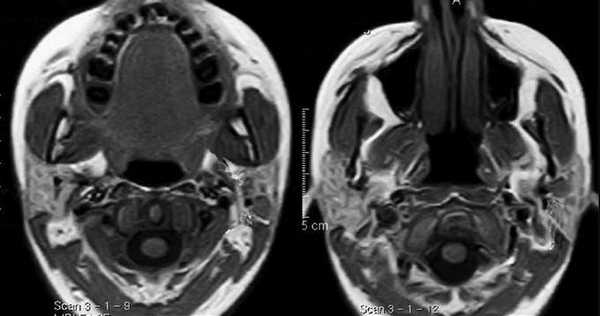

С помощью КТ сложно было выявлять опухоли малых размеров (Т1стадия) и их границы в результате низкой контрастности, а также новообразования с поверхностным распространением (рис. 1). Вместе с тем, 72,0% обследованных больных имели Т3, Т4 стадии опухолевого процесса и после болюсного введения контрастного вещества контрастность опухоли повышалась. С увеличением размера опухоли отмечалась неоднородность усиления из-за наличия некроза (рис. 2). Жировые пространства подъязычной области в нормальном состоянии представляют собой симметричную зону низкой плотности между челюстно-подъязычной и подбородочно-подъязычной мышцами. Облитерация жировых пространств подъязычной области служила основным показателем опухолевого поражения при выявлении небольших образований дна полости рта (рис. 3,4).

Рис.1. Пациент Ж., 58 лет. МСКТ ротоглотки в аксиальной проекции: А - нативное исследование, В - с внутривенным болюсным контрастированием. Небольшая инфильтративная опухоль ротоглотки (левой небной миндалины Т1 стадии). Границы опухоли не дифференцируются, накопление контраста слабое (показатели плотности в нативной фазе исследования 45 ед.Н, после внутривенного болюсного усиления - 56 ед.Н). Определяется смещение левой стенки ротоглотки, сглаженность контура (стрелки)

Рис. 2. Пациент К., 65 лет. МСКТ полости рта с внутривенным болюсным контрастированием в аксиальной проекции. Опухоль передних отделов дна полости рта Т4 стадии. Выявляется опухолевое образование размерами 4,5х3,5 см (стрелки) неоднородной структуры. Отмечается инвазия опухоли в нижнюю челюсть

Рис.3. Пациент Ч.,54 года. МСКТ в аксиальной проекции с внутривенным болюсным контрастированием. Небольшая опухоль дна полости рта с переходом за среднюю линию (стрелки). Инфильтрация жировых пространств дна полости рта

Рис.4. Пациент П., 48 лет. МСКТ полости рта с внутривенным болюсным контрастированием. В передних отделах дна полости рта центрально и слева дифференцируется участок низкой плотности размерами 0,8х0,4 см (стрелки). Накопление контраста слабое, показатели плотности 65-67 ед.Н. Границы опухоли четко не определяются, при этом распространения за среднюю линию не обнаружено. Отмечается облитерация жировой клетчатки подъязычной области слева. Справа жировые прослойки дифференцированы, мышцы не изменены. Лимфатические узлы шеи не увеличены

Сложно было выявлять опухоли малых размеров (Т1,Т2 стадии), расположенные в передних отделах дна полости рта из-за расположенных рядом костных тканей, зубов, наличия пломбировочного материала вследствие выраженных артефактов от плотных структур. В ряде случаев визуализацию облегчало наличие язвенного дефекта в структуре опухоли (рис. 5). При всех опухолях Т3, Т4 стадии определялось повышение плотности после введения контрастного вещества, их края четко визуализировались относительно окружающих тканей. Во всех случаях Т3, Т4 стадии удавалось определить размер опухоли и оценить инфильтрацию и распространение в соседние зоны, а также за среднюю линию (рис. 6).

Особенностью МРТ являлась высокая контрастность мягких тканей. Плотные костные ткани или зубоврачебный материал не создавали артефактов, что давало возможность получать четкое изображение опухоли полости рта, определять распространение в мягкие ткани, глубокие отделы орофарингеальной зоны, в область неба. На Т1-ВИ все опухоли имели ту же интенсивность сигнала, как у окружающих мышц или слабее (рис.7).